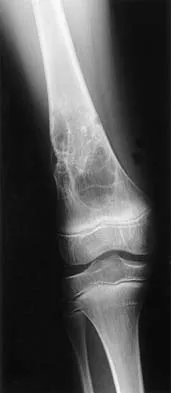

Figures 12a and 12b show the radiographs of a 50-year-old patient who reports acute knee pain after sustaining a twisting injury while playing tennis. Examination is unremarkable. The next most appropriate step in management should consist of

Explanation

The radiographs show localized diffuse cortical thickening that is characteristic of melorheostosis. The condition may be monostotic or it may involve many bones in one extremity (monomelic) in the distribution of a sclerotome. Bone scans will show increased uptake at the site or sites of skeletal involvement. Long tubular bones are most commonly involved. Melorheostosis is usually asymptomatic and requires no treatment. On rare occasions, there may be associated soft-tissue contractures. Dorfman H, Czerniak B: Bone Tumors. St Louis, MO, Mosby Inc, 1998, pp 1105-1107. Campbell CJ, Papademetriou T, Bonfiglio M: Melorheostosis: A report of the clinical, roentgenographic, and pathological findings in fourteen cases. J Bone Joint Surg Am 1968;50:1281-1304.